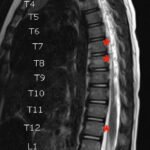

Pediatric neuroblastoma is famously characterized by an abdominal mass in a toddler with “raccoon eyes,” Horner syndrome, and/or opsoclonus myoclonus. However, rare cases may present with non-discrete symptoms and signs which create challenges for timely diagnosis. This case depicts a toddler with bulbar symptoms, including bilateral ptosis, dysphagia, drooling, head tilt and ataxia in a post-viral course mimicking other neurologic diagnoses, including myasthenia gravis. Magnetic resonance imaging (MRI) of the brain and spine uncovered a right adrenal mass along with heterogenous enhancement in multiple vertebral bodies and the clivus, consistent with metastatic disease. A diagnosis of neuroblastoma was confirmed with elevated homovanillic acid (HMA) and vanillylmandelic acid (VMA) levels and adrenal biopsy. The patient was treated with plasmapheresis for suspected paraneoplastic neurological syndrome and subsequent chemotherapy. In this case presentation, we review neurologic syndromes causing acute-onset pediatric bulbar weakness along with the patient’s key MRI findings.